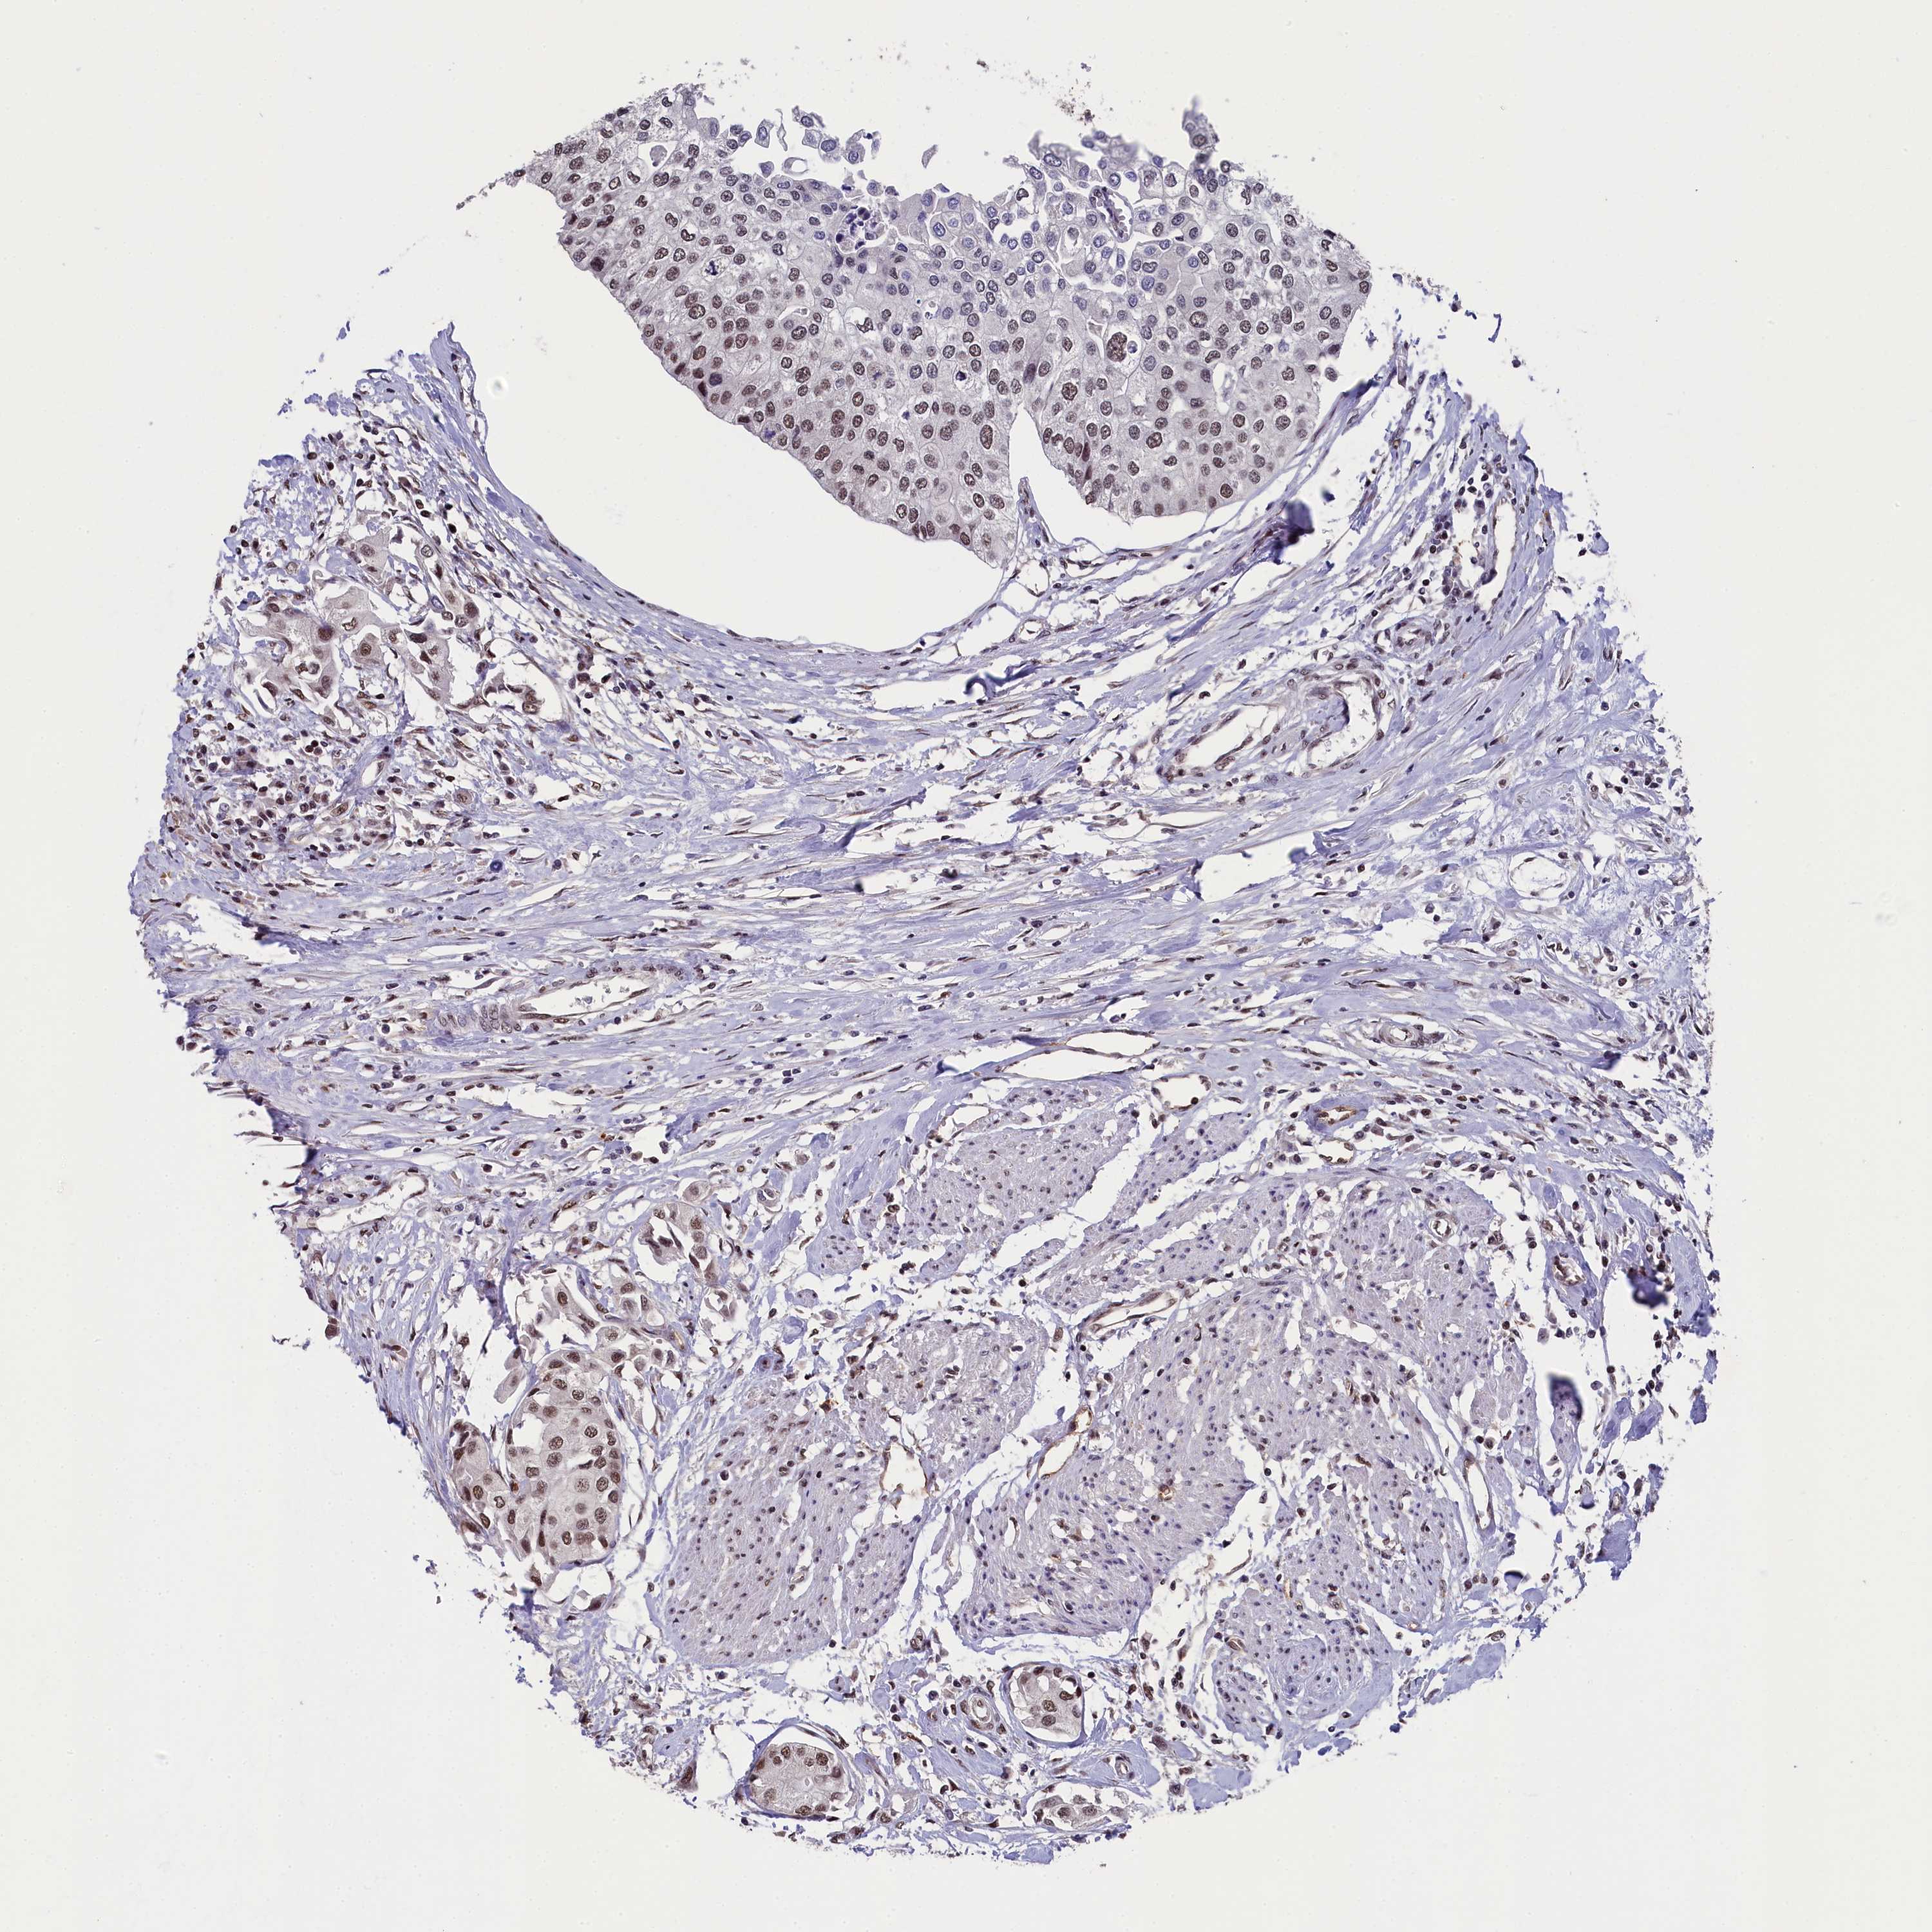

UROTHELIAL CANCER - Protein expressioni

A mouse-over function shows sample information and annotation data. Click on an image to view it in a full screen mode. Samples can be filtered based on level of antibody staining by selecting one or several of the following categories: high, medium, low and not detected. The assay and annotation is described here.

Note that samples used for immunohistochemistry by the Human Protein Atlas do not correspond to samples in the TCGA dataset.

Antibody stainingi

Antibody staining in the annotated cell types in the current human tissue is reported as not detected, low, medium, or high, based on conventional immunohistochemistry profiling in selected tissues. This score is based on the combination of the staining intensity and fraction of stained cells.

Each image is clickable and will lead to virtual microscopy that enables deeper exploration of all samples and also displays staining intensity scores, fraction scores and subcellular localization as well as patient and tissue information for each sample.

Antibody HPA041124

Staining

High

Medium

Low

Not detected

Intensity

Strong

Moderate

Weak

Negative

Quantity

>75%

75%-25%

<25%

None

Location

Nuclear

Cytoplasmic/membranous

Cytoplasmic/membranous,nuclear

Urothelial carcinoma, High grade